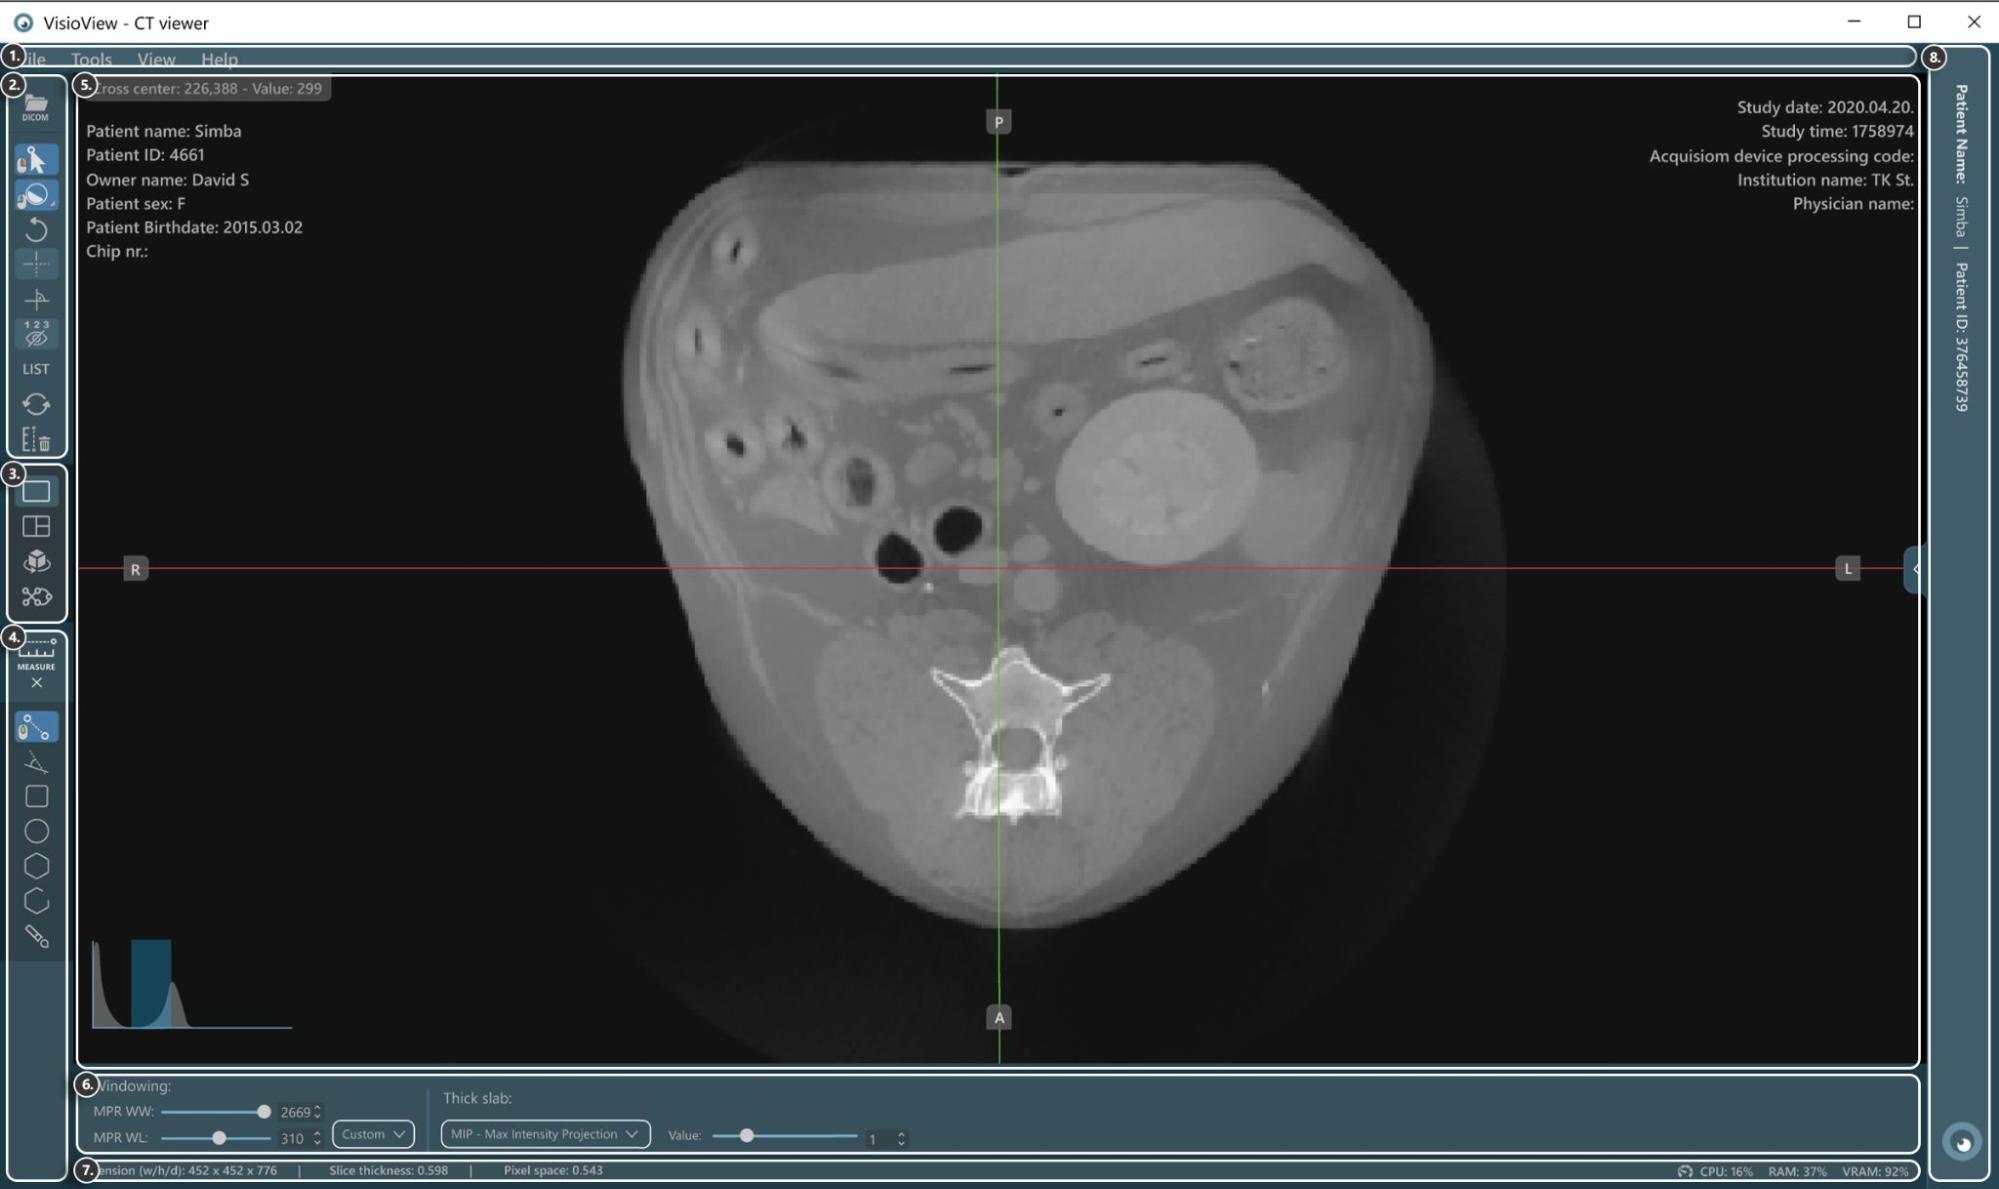

Abschnitte des VisioVIEW CT-Viewers¶

Der VisioVIEW CT-Viewer besteht aus mehreren Abschnitten, die jeweils einem bestimmten Zweck dienen. Im Folgenden finden Sie eine detaillierte Beschreibung jedes Abschnitts.

DICOM-Datei laden

Element auswählen

Windowing-Werkzeug (Standard, Dynamisch oder Auswahl aus vorhandenen Windowing-Voreinstellungen)

Bild drehen

Slicer einblenden/ausblenden

Senkrechte/Getrennte Slicer

Messinformationen ausblenden/anzeigen

Messungsliste öffnen

Bildtransformationen auf Standard zurücksetzen

Alle Messungen löschen

Ansichts-Selektor¶

Messwerkzeuge¶

Messwerkzeuge ein-/ausblenden

Abstandsmessung

Winkelmessung

Rechteckmessung

Ovalmessung

Polygonmessung

Pfadlängenmessung

Pinselwerkzeug

Viewer-Bereich¶

HU (Hounsfield-Einheit) Pixelwert

Patienteninformationen

Histogramm-Werkzeug für Windowing

Slicer

Studieninformationen

Anzeigeeinstellungen und Optionen¶

Windowing-Einstellungen

Einstellungen für dicke Schichten

Informationsleiste¶

DICOM-Bild- und Auflösungsinformationen

Leistungs und Ressourcennutzungsinformationen